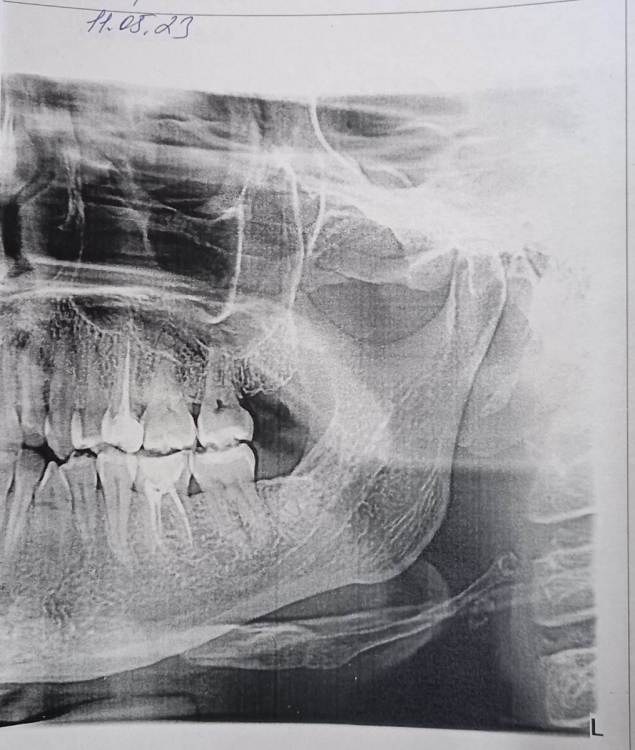

Mariaduya Опубликовано 5 июля, 2023 Поделиться Опубликовано 5 июля, 2023 (изменено) Здравствуйте. У меня сложная ситуация, боли в челюсти практически 1.5 года. Врачи не видят проблем, уже не знаю куда обратиться. Хронология. 1. В ноябре 2021 начал слегка болеть 1.6 зуб. В стоматологии мне его сразу начали депульпировать, без снимка. В ходе лечения не болел, как запломбировали каналы, постепенно появилась ноющая, постоянная боль. Я обратилась снова, сказали, что на зубе есть хроническое воспаление и ввели антибиотик туда при помощи электрофареза. Среагировал 2.5 зуб с другой стороны, и тоже начал постоянно болеть, он был депульпирован давно, но в нем развился большой кариес. 2. Мне начали их перелечивать. 1.6. не получилось пройти канал, залили резодентом, 2.5 просто переличили. 3. Боль все ещё осталась, уже в двух зубах. Врачи ничего не знают, отправили к неврологу, ЛОРУ и т.д. 4. Обошла неврологов, лоров, делала мрт, кт с контрастом головы, пазух носа, все ок. Невролог выписывает финлепсин, не помог. 5. Делала в частной клинике кт зубов, без описания, ещё не знала, что оно нужно, врач посмотрела и сказала, что видит небольшое, хроническое воспаление на 1.6 зубе и все, а так она не знает. 6. И так 1.5 года никто не знает, что со мной. Боль 1.6 и 2.5 зубы, начинают и нижние зубы болеть, уже и ухо болит. После орви болит все очень сильно, что хочется уже не просыпаться. Удалять их говорят не показаний, вдруг боль останется. Снимки в хронологии выкладываю. Есть ли на них воспаление 1.6 зуба, 2.5 зубов, есть ли них кисты свищи и все что угодно, что аномально и может вызывать боль. Может что-то с надкостницой, или суставами. Все что у меня есть - интернет, так как живу я очень далеко от нормального города и доступна только городская поликлиника, где врачи говорят, что это неврология, а невролог говорит наоборот. Сами зубы болят странно, по очереди. Если болит неделю 1.6 зуб, то 2.5 не болит и так наоборот. Вместе они не болят. Ещё странное то, что они практически симметричны друг другу по расположению. Изменено 5 июля, 2023 пользователем Mariaduya Ссылка на комментарий

Carioznik Опубликовано 5 июля, 2023 Поделиться Опубликовано 5 июля, 2023 Здравствуйте, 27 зуб надо внимательнее посмотреть, возможно там пульпит (но это неточно "бумажные " снимки малоинформативны). Скиньте лучше КТ или хотя бы ОПТГ но в электронном формате(а не фото распечатки на бумаге) Ссылка на комментарий

Carioznik Опубликовано 13 июля, 2023 Поделиться Опубликовано 13 июля, 2023 по этому старому КТ: на 16 - есть пропущенный канал, от этого, на одном из корней - есть небольшой воспалительный процесс (на тот момент). "Само не заживет", будет только расти, может, на сегодняшний момент - уже стал большой). Но жалобы в таких случаях обычно другие. Делайте новое КТ (по старому только гадать...) и снова, очный осмотр стоматолога, явно понадобится. 1 Ссылка на комментарий